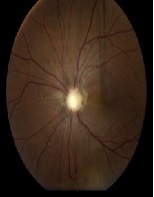

Acute Cerebral Venous Thrombosis with Papilledema and Complete Vision Loss

Dante Sorrentino, Anagha Medsinge*, Luis Gonzalez-Gonzalez, Gabrielle Bonhomme